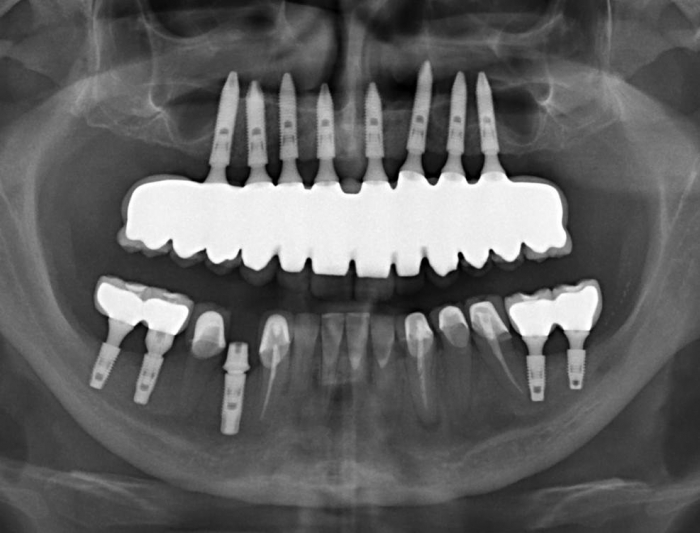

Raio X inicial

Raio X final com prótese fixa superior em porcelana e zircônia sobre implantes Cone Morse